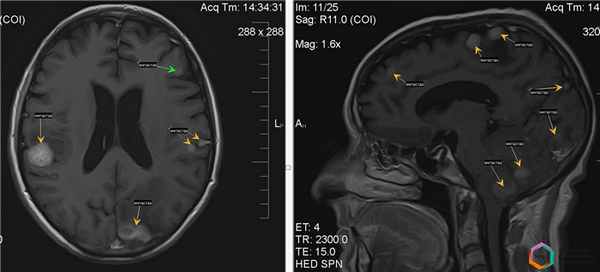

Рис.7 Результат стажированной радиохирургии крупного (4 см) метастаза почечно-клеточного рака.Слева: опухоль в глубинных отделах левой височной доли с ростом в височный рог левого бокового желудочка, с начальной компрессией левой ножки мозга. Справа: через 8 месяцев после второго сеанса облучения. Полный регресс метастаза. Видны крупные магистральные артерии, ранее вовлеченные в опухоль.